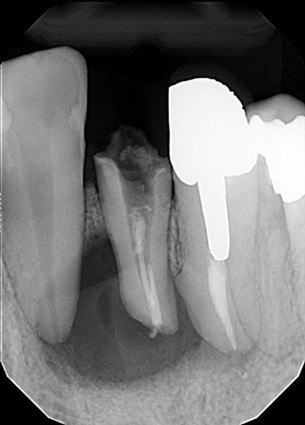

| 主訴 | 膿がたまてしまっていて痛い状態 |

| 状態 | 歯をとった瞬間に黄色い膿が吹き出た |

| 治療内容 | 根先部が破壊されてしまっていて、治療が難しい状態だったがマイクロスコープによる根管治療と、MTAセメントでの根幹充填により症状が緩和された。 骨再生因子を用いて骨を再生し、5ヶ月後には骨の再生が完了。セラミックによって審美的に補綴をして終了したケース。 |

| 料金 | 抗菌性歯内両方10万円、ファイバーコア2万円、ジルコニアクラウン12.5万円→14.5万円+税 |

※消毒費用が別途かかることがあります